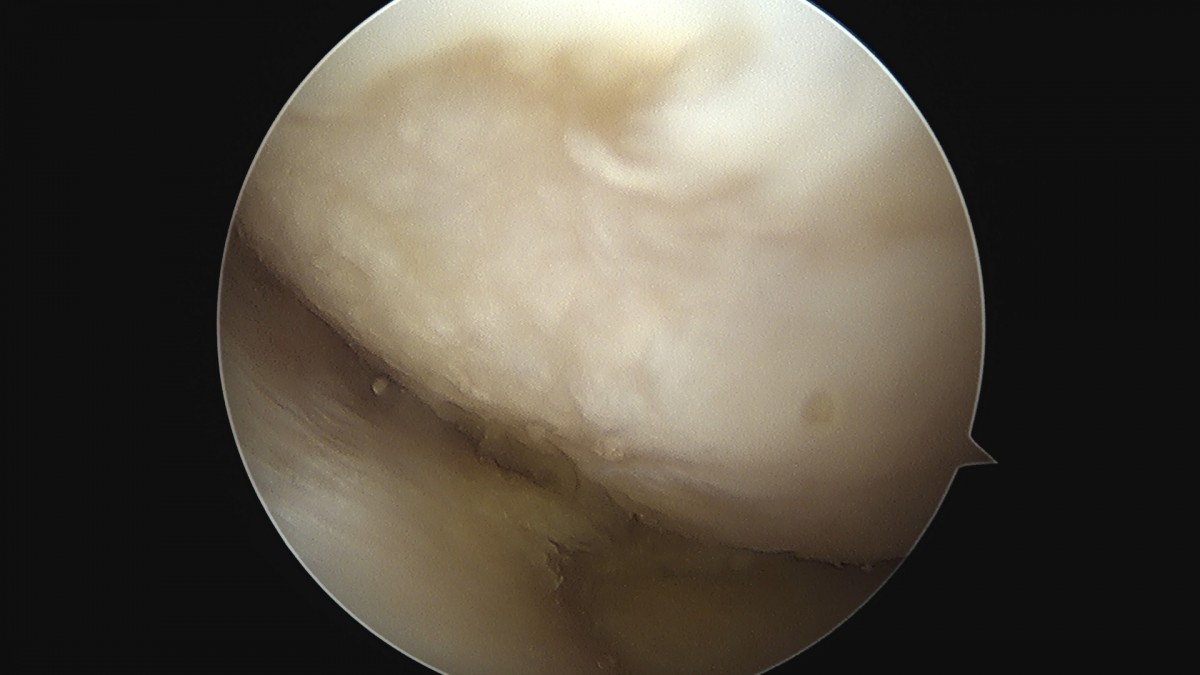

이재상원장님 무릎 반월상 연골판 절제술 안경O 환자

작성자 최고관리자 댓글 0건 조회 374회 작성일 25-09-16 15:58